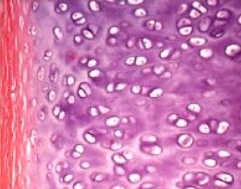

J'ai un bug a propos de l'image portant sur ce QCM

L'intitulé est "a propos des groupes isogeniques coronnaire"

L'image ne représente pas des groupes isogeniques axiaux ???

L'image aurait représenté des groupes isogéniques axiaux s'ils étaient bien tous alignés dans un sens

Là, ils s'égaillent un peu partout, il y en a même qui partent à 90° donc bon ^^

En fait en agrandissant c'est même exactement cette image :clown:

image.jpg (21.89 Kio) Vu 397 fois

la bonne, c'est que je vous accorde une double correction sur ce QCM parce qu'effectivement, ce sont des groupes isogéniques axiaux et que l'énoncé n'était pas en rapport. Ensuite, sachez que si cet item était tombé au concours, la correction aurait été cette que j'ai donné, c'est à dire que Philip ne fait pas attention à la corrélation QCM/ énoncé; genre l'an dernier il a fait tomber une image d'os long en disait que c'était un os cours mais il a fait le QCM en rapport avec les os longs et les items concernants les os longs était justes.